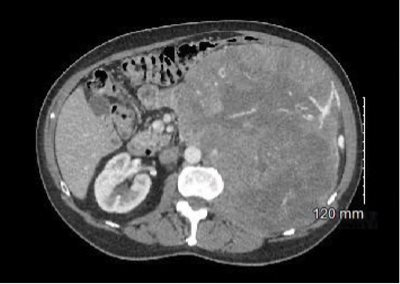

The CT scan impression is as follows: “Huge heterogeneous vascular left-sided retroperitoneal mass displacing adjacent structures and likely renal in origin. Findings most likely represent a renal cell carcinoma.”

The mass is noted to be at least 25 cm in diameter per the radiologist’s interpretation (see Fig. 1), and the left kidney and other local structures are noted to be anteriorly displaced (see Fig. 2).

Fig. 2. CT abdomen with contrast. Left kidney with anterior displacement due to mass along with other local structures.